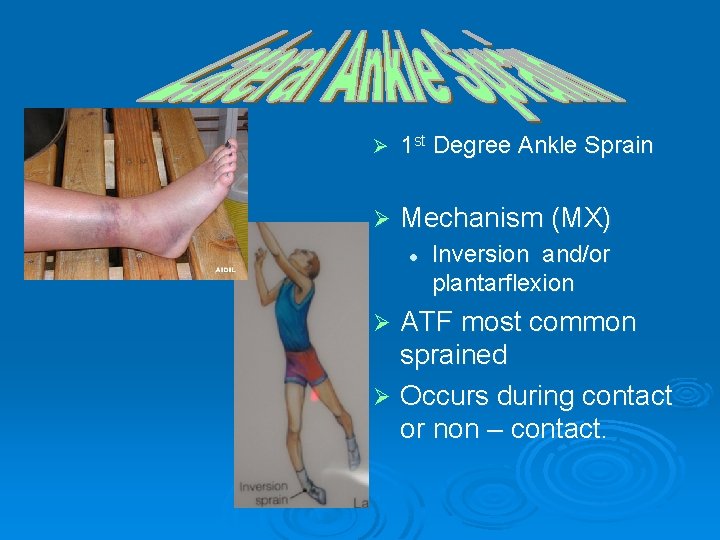

Ø 1 st Degree Ankle Sprain Ø Mechanism (MX) l Inversion and/or plantarflexion ATF most common sprained Ø Occurs during contact or non – contact. Ø

v S/S v 1 st v v v degree Mild pain Pt – ATF Possible swelling Fast recovery to FWB and ROM No joint laxity